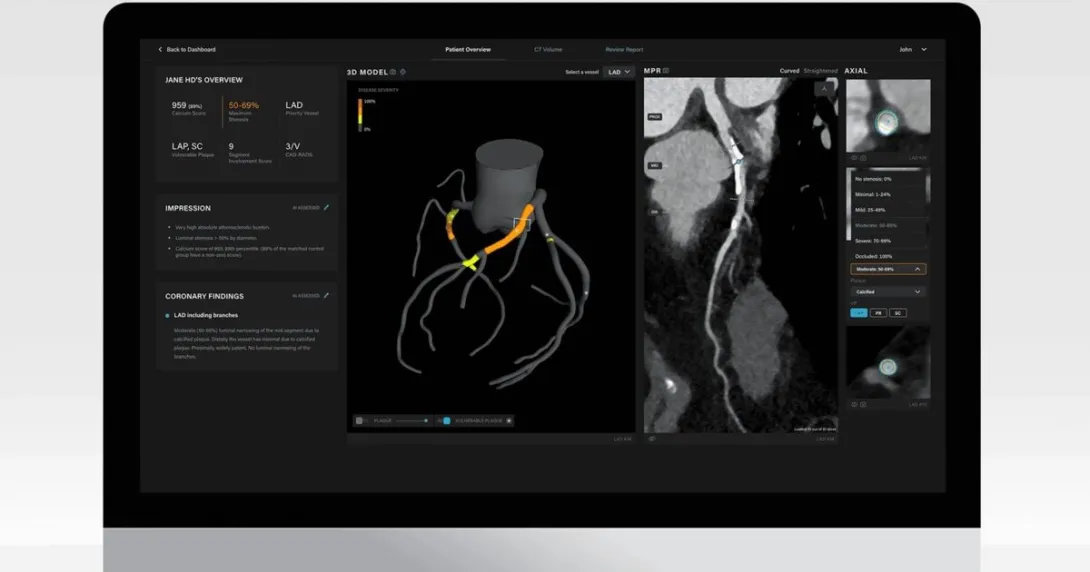

Artrya secures UK, EU approvals for Salix

Within a week, ASX-listed medtech company Artrya received both regulatory approvals from the European Union and the United Kingdom for its Salix Coronary Anatomy product.

The AI-powered software identifies and analyses arterial plaque to diagnose coronary artery disease.

The recent certifications allow Artrya to market Salix in 28 EU member countries and in the UK, where it already has a four-year contract to supply 1,250 National Health Service Trust hospitals with the product.

These approvals also represent a win for the company after having a major setback in June when the US Food and Drug Administration rejected its initial 510(k) application for its software product.

Meanwhile, Salix is now geared for commercial rollouts in Australia and New Zealand after securing clearances over the past two years.